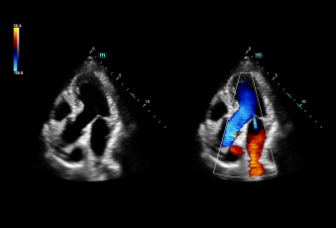

Consona presenta soluzioni nuove e concrete, che aiutano a effettuare diagnosi efficaci con semplicitĂ , rivolgendosi a un'ampia platea di pazienti. La serie mette a disposizione strumenti estremamente avanzati per rimanere all'avanguardia nella diagnosi cardiovascolare.

Galleria di immagini